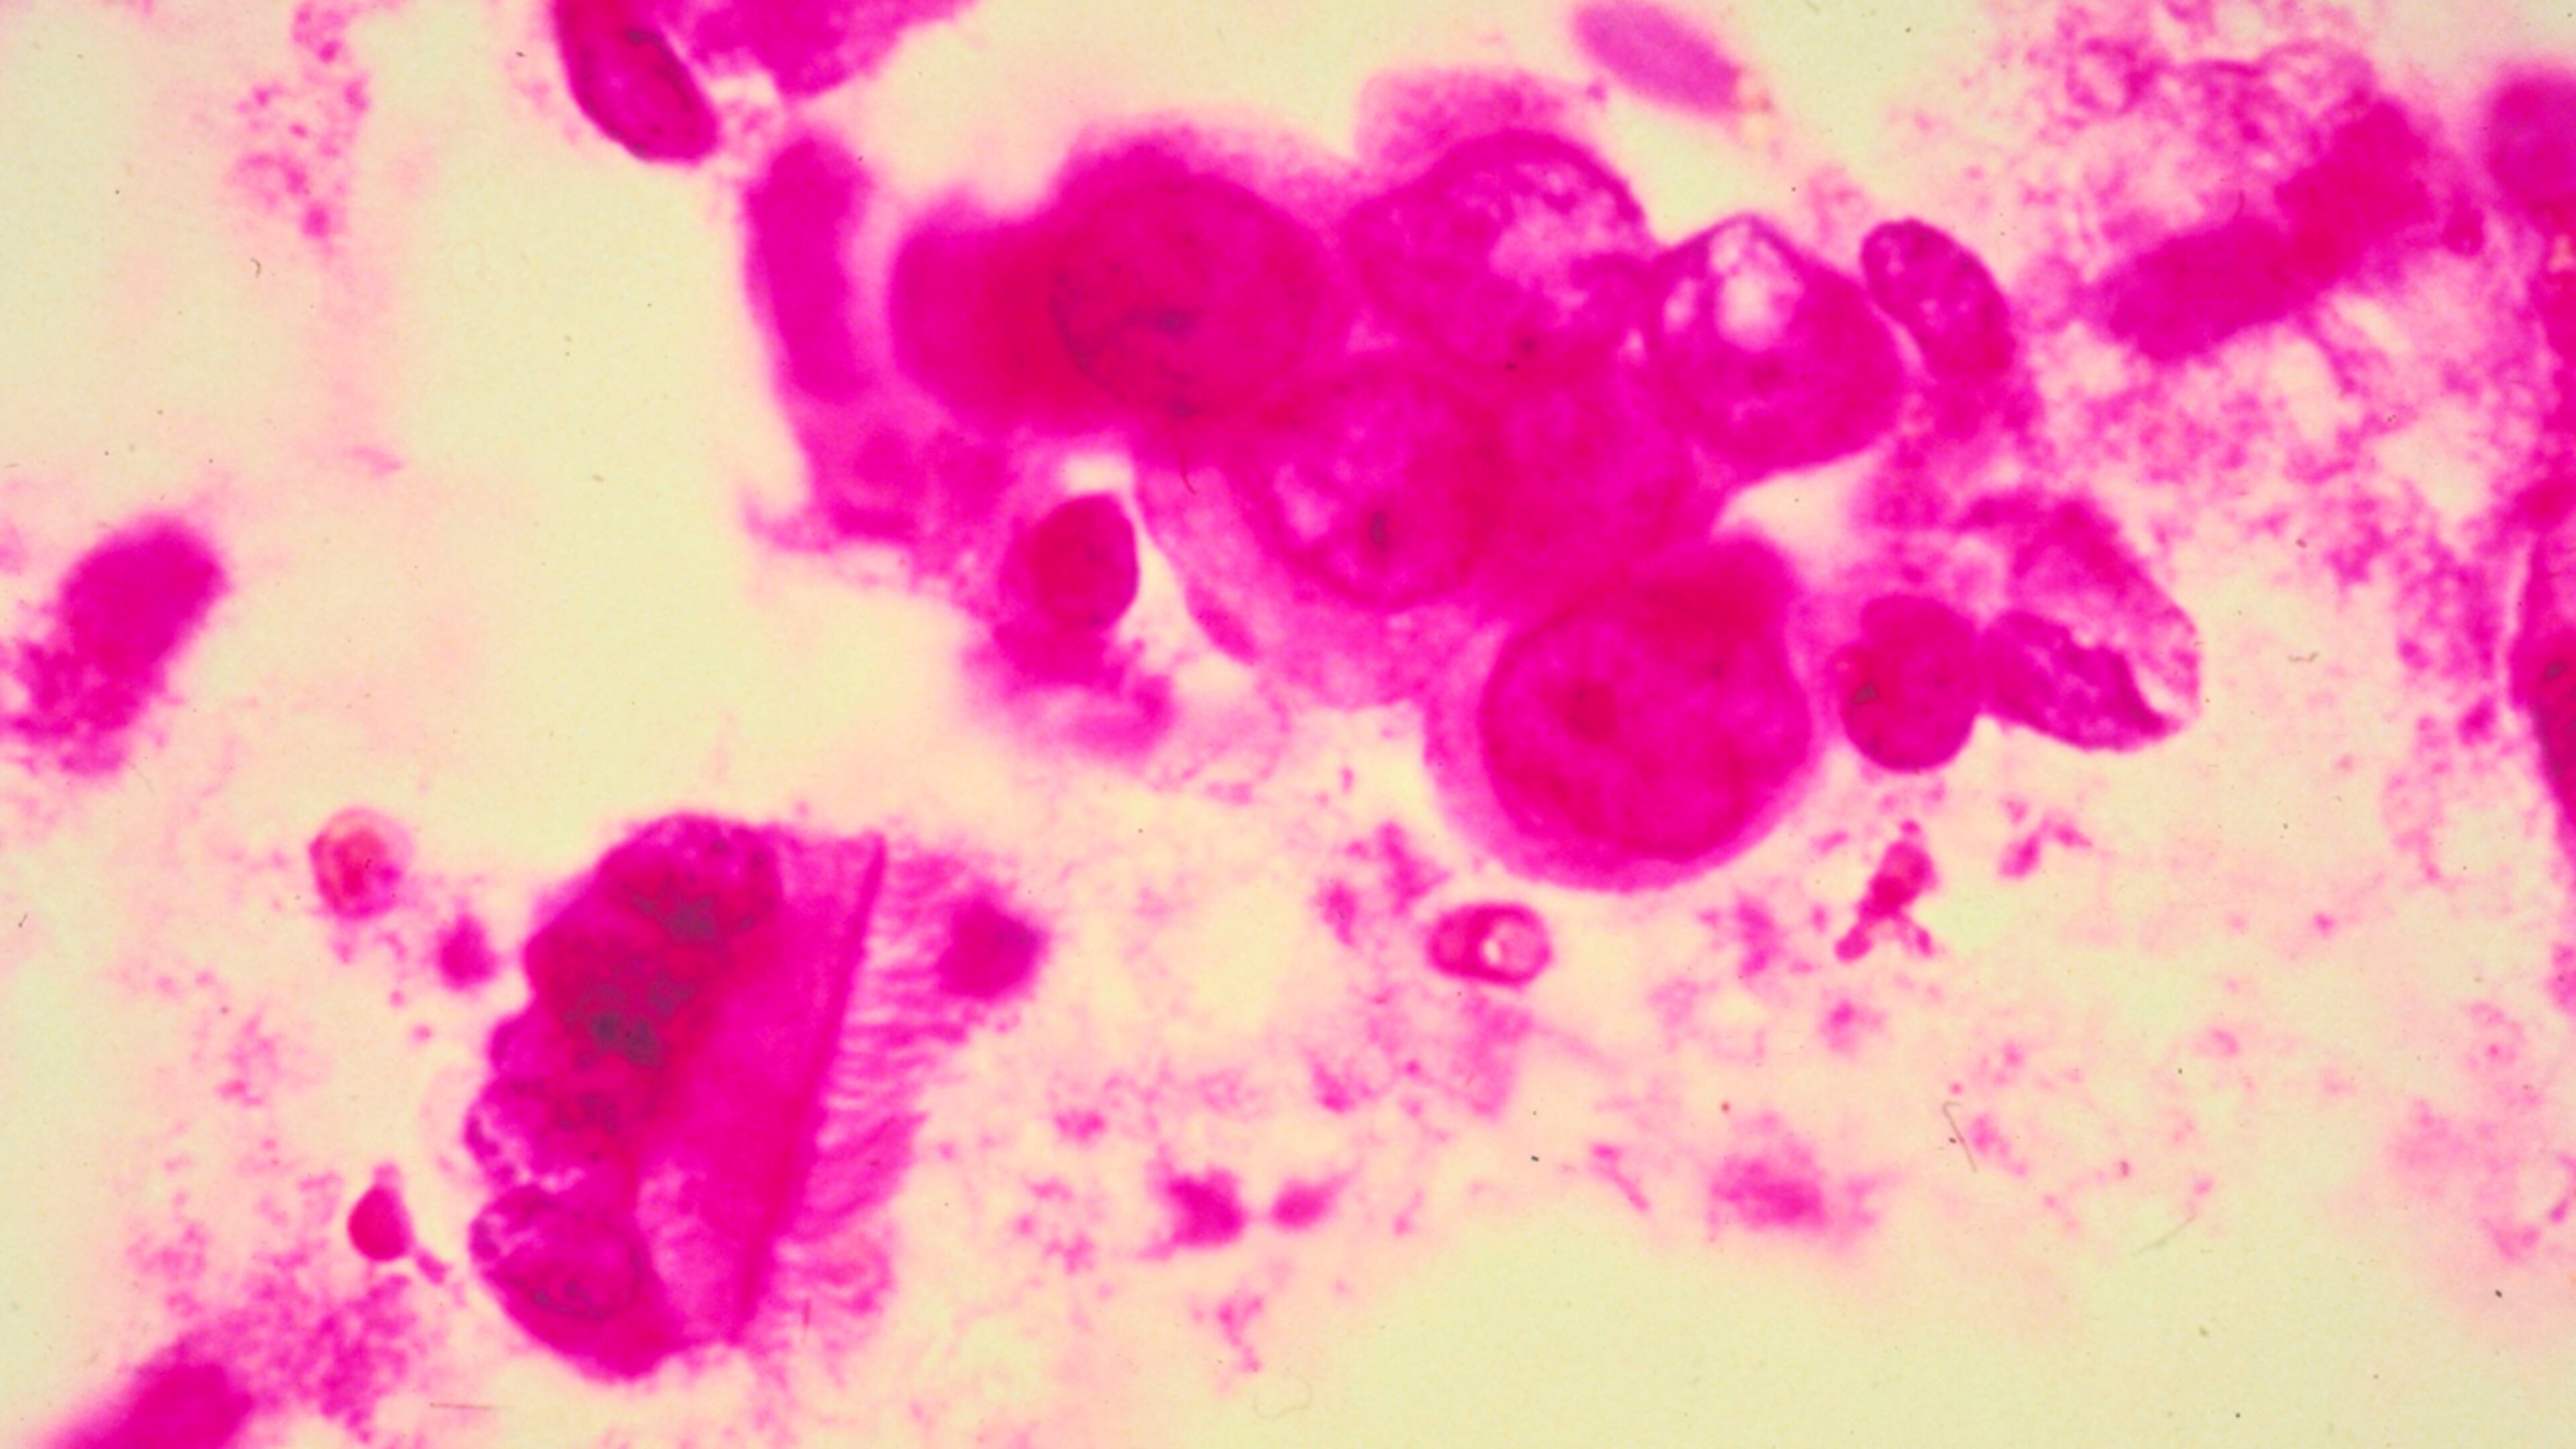

Tecentriq was approved Friday for treating advanced triple-negative breast cancer, The Associated Press reported.

Triple-negative accounts for about 15 percent of cases of breast cancer.